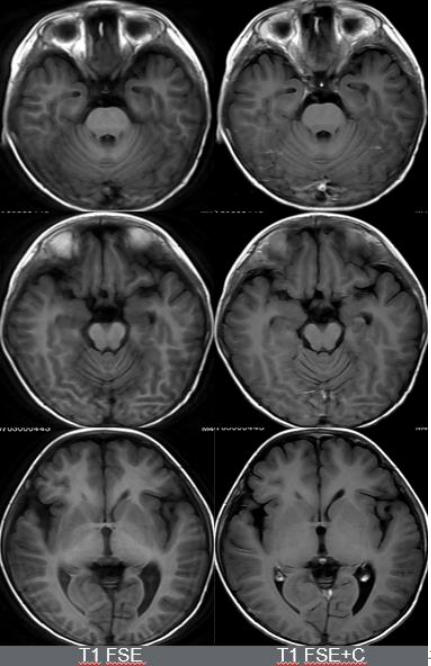

MR三把利器:平扫,增强,结合临床。难道这个病例最后也是结合临床?20210707,第三次MR检查;3D ASL提示,双侧额叶灌注增加

MUSE DWI 1000,168 × 264,提示双侧额叶皮层弥散受限。

除此之外,海马的信号怪怪的,是什么?所以,我们加扫海马矢状位小视野弥散。